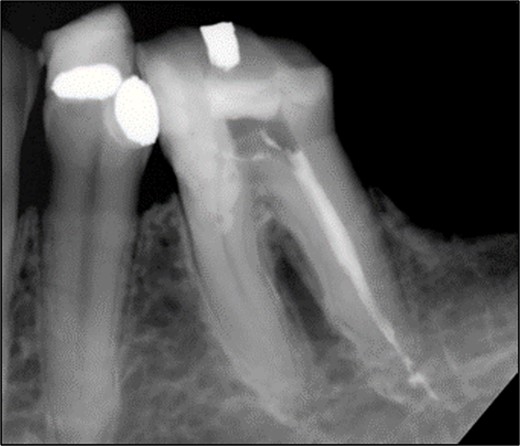

Non-surgical root canal treatment was initiated under local anesthesia and rubber dam isolation. Pulp extirpation was performed on all canals (mesio-buccal (MB), mesio-lingual (ML), and distal (D)). The MB and ML canals were instrumented using ProTaper Gold files and obturated with a bioceramic sealer (iRoot SP). The orifices were sealed with glass ionomer cement (Fuji IX) (Fig. 3).

Periapical radiograph of tooth 36 with obturation on MB and ML canals.